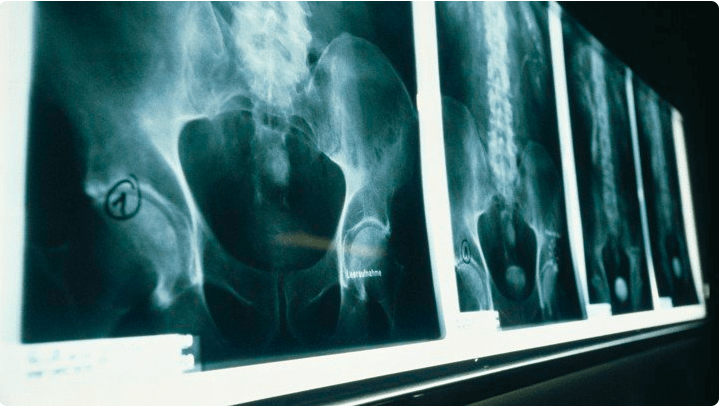

While this kind of “pain without lesion” has long puzzled doctors, the 19th century ushered in a whole new era of controversy, argues the bioethicist Daniel Goldberg in his paper, “Pain, objectivity and history: understanding pain stigma.” The era also brings technological developments—“objective” instruments like the X-ray—that rendered previously unseeable injuries seeable.

Zhang: You write, “Objectivity has a history.” Why does the idea of “objectivity” emerge specifically in the 19th century? You have new technology, like X-rays, and this idea of “mechanical objectivity,” right?

Goldberg: Mechanical objectivity basically says, if you want to know the truth of the matter as it exists in nature, the way is to remove all human influence from that object—to make it look just as it appears.

With these scientific imaging techniques—stethoscopes, photographs, X-ray, microscopes—the point of all these is to locate the natural objects of disease. How do we know whether or not this particular illness complaint is true? The answer is we can connect the patients symptoms to material pathologies in objects that we can image. That’s how we can distinguish truth from falsities.